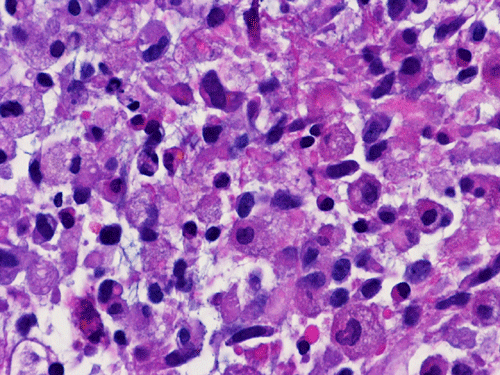

He was admitted again. In this admission, he developed left intraparenchymal hemorrhage associated with the enhancing mass, edema, and 0.4 cm left to right midline shift. A craniectomy was performed to evacuate the blood and biopsy the enhancing mass. The followings are representative images from the biopsy material.

Panel A to E are intra-operative cytologic preparation, Panel E to J are frozen section, Panel K to N are permanent sections.